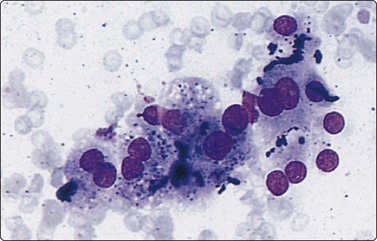

Purulent material aspirated from a focal lesion should always be subjected to microbiological investigation. Routine smears should also be prepared and screened for neoplastic cells, as tumor metastases, for example from a primary bowel adenocarcinoma, can undergo central necrosis, simulating an abscess. Pyogenic abscess demonstrates a marked neutrophil infiltrate, with necrotic debris.93 Hepatocytes from the periphery of the abscess may show considerable atypia.76 The predominant organism in pyogenic abscesses is Klebsiella.93 Amebic abscess due to Entamoeba histolytica, with contents likened to anchovy paste (thick reddish-brown semi-fluid material), shows abundant necrosis with fewer inflammatory cells. Trophozoites are not found in the central necrotic area; they should be sought in the viable periphery of the abscess (Fig. 10.11).93,94 They are globular organisms, with an eccentric spherical nucleus showing a central clear zone with a dot-like karyosome and margination of chromatin. The cytoplasm is vacuolated and contains ingested red blood cells. Amebae stain positive with PAS. They resemble foamy macrophages and may be missed if not suspected. The diagnosis of hepatic actinomycosis by FNB has been reported.95,96 It occurs in a background of systemic actinomycosis, secondary to pulmonary or uterine primary sources of infection.

image

Fig. 10.11 Amebic abscess

Single trophozoite with a small peripheral nucleus (upper left); background of acute inflammatory cells (Pap, HP).